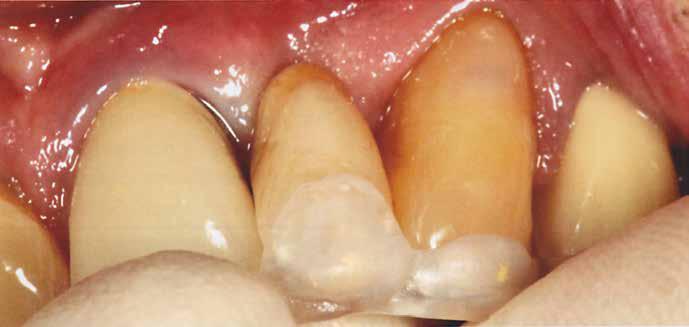

Végezetül részletfelvételek egy másik ragasztott hídról, amely hasonló módon készült, hat hónappal a behelyezés után (42–43. képek)

A hídtag enyhe mozgathatósága miatt az íny stimulálva volt. Ezzel a vérellátás további segítséget kapott, ami a lágyszövet kiváló adaptálódását hozta magával.